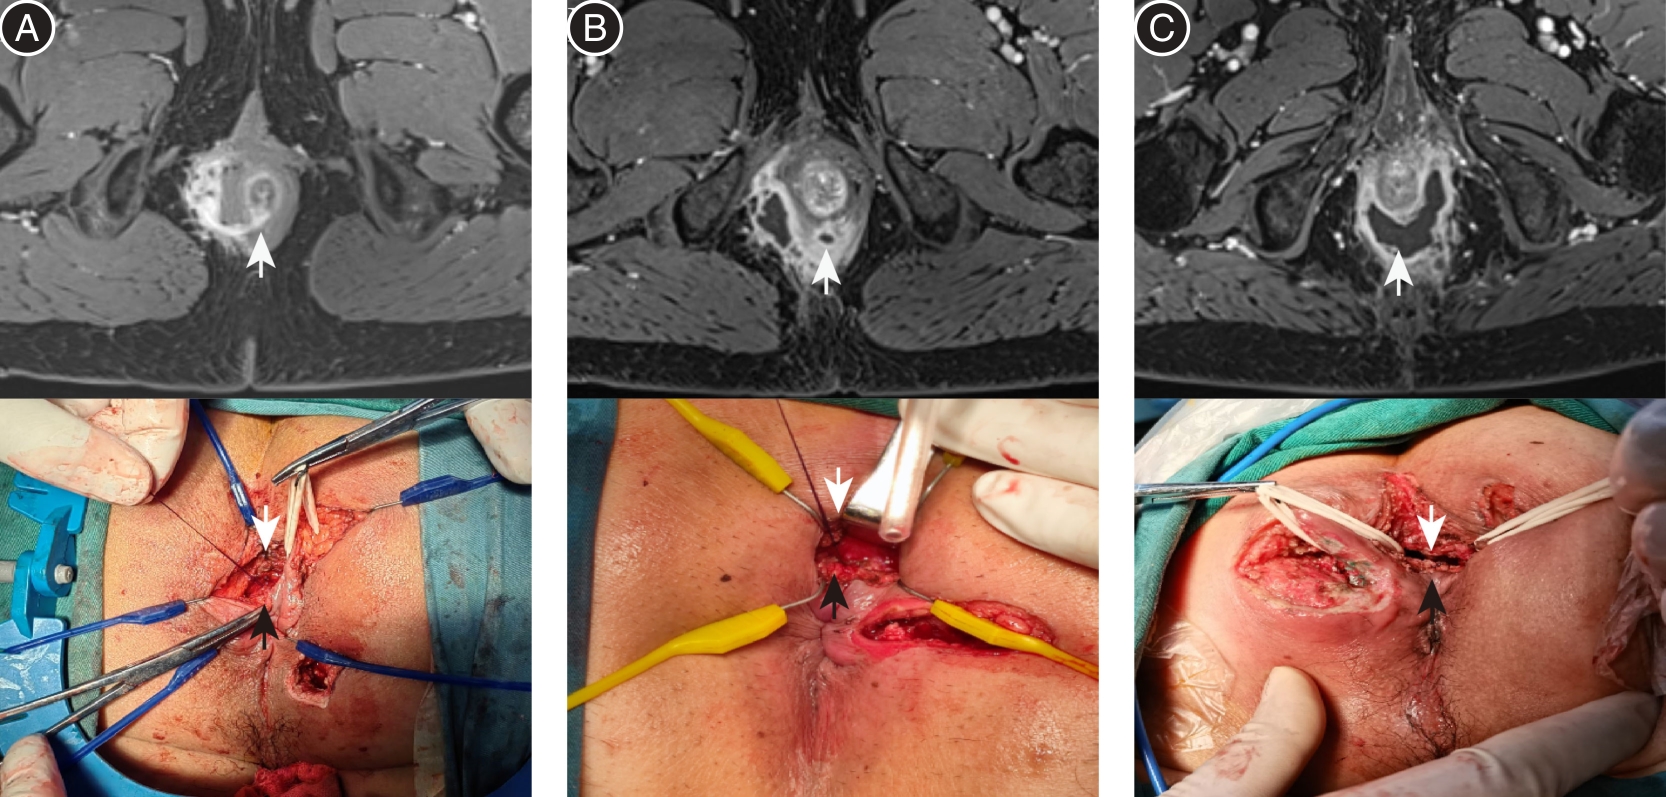

Zhilong SI,Hao WANG,Fei XIAO. Feasibility of modified LIFT guided by magnetic resonance imaging in the treatment of deep anorectal abscess[J]. The Journal of Practical Medicine, 2025, 41(1): 65-70.